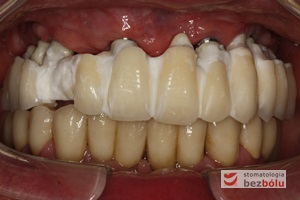

Wprowadzenie gotowych koron na zęby i implanty - śruby łączników tytanowych zamknięte różową gutaperką

Wprowadzenie gotowych koron na zęby i implanty – śruby łączników tytanowych zamknięte różową gutaperką